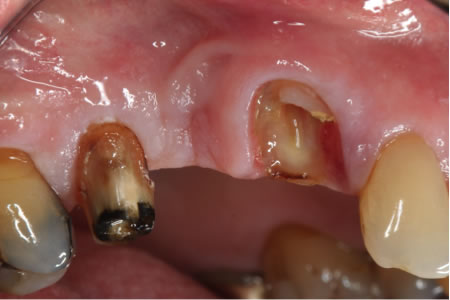

Before – A failed bridge left teeth broken to the gumline